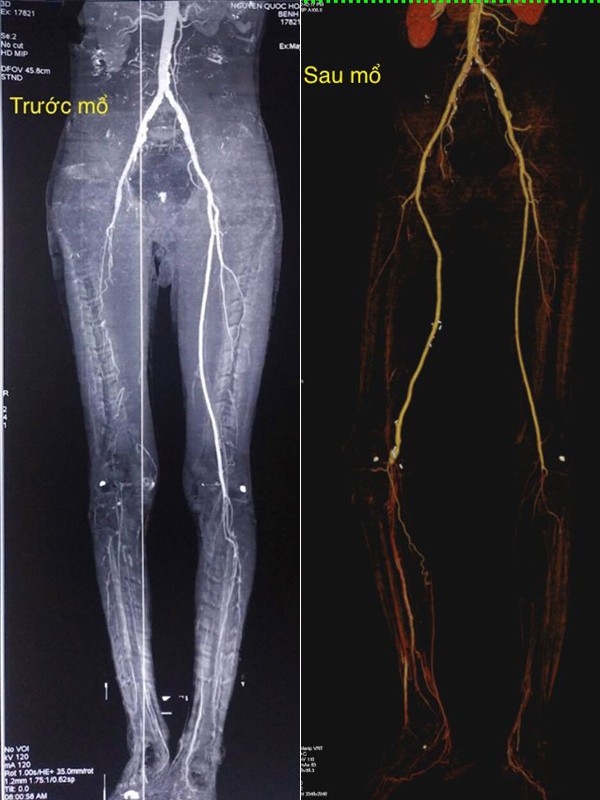

Qua khám lâm sàng và chẩn đoán hình ảnh, các bác sĩ khoa Phẫu thuật Tim mạch kết luận, bệnh nhân bị tắc hoàn toàn động mạch đùi nông và động mạch khoeo do hút thuốc lá nhiều. Nếu phẫu thuật hoặc can thiệp nội mạch thông thường, mạch không có khả năng tái thông.

Do cuối động mạch khoeo vẫn còn 4 nhánh bàng hệ của vòng nối quanh gối nên các bác sĩ đã phẫu thuật bóc nội mạc động mạch khoeo, làm cầu nối động mạch đùi – động mạch khoeo chân phải bằng tĩnh mạch hiển tự thân đảo chiều.

Sau phẫu thuật gần 1 tháng, tình trạng của bệnh nhân cải thiện rõ rệt, chân phải đã hồng, ấm, tưới máu cẳng – bàn chân tốt. Bệnh nhân đã có thể đi lại, vận động được.